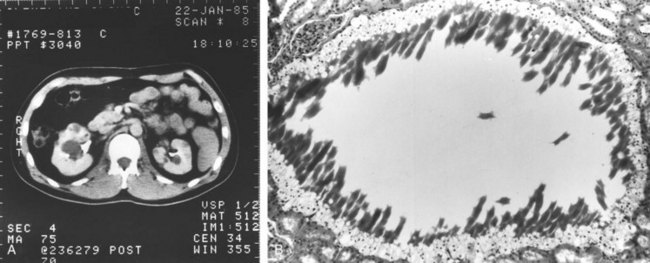

MRI is a noninvasive and accurate modality for demonstrating both the presence and the cephalad extent of vena caval involvement and has been the preferred diagnostic study at most centers for the past few decades (Goldfarb et al, 1990; Kallman et al, 1992; Bechtod and Zagoria, 1997; Choyke, 1997; Oto et al, 1998; Sun et al, 1999). Administration of gadolinium during the study often allows tumor thrombi to be differentiated from bland thrombus, because the latter does not demonstrate enhancement. More recent evidence suggests that multiplanar CT can provide essentially equivalent information, including delineation of the cephalad and caudal extent of the thrombus (Fig. 49–26) (Pretorius et al, 2000; Choyke et al, 2001; Bassignani, 2006; Zhang et al, 2007a; Bach and Zhang, 2008; Ng et al, 2008; Herts, 2009). The importance of high-quality preoperative imaging cannot be overemphasized and should be obtained as close as possible to the date of surgery because progression of the tumor thrombus may mandate important changes in intraoperative management (Blute et al, 2004b; Wotkowicz et al, 2008).

Figure 49–26 CT scan demonstrating lower pole right renal cell carcinoma (small arrows) with level III inferior vena cava (IVC) thrombus. The large arrow indicates the upper extent of the tumor thrombus within the intrahepatic portion of the IVC. The arrowhead indicates extensive retroperitoneal venous collateral vessels associated with restricted flow within the IVC.